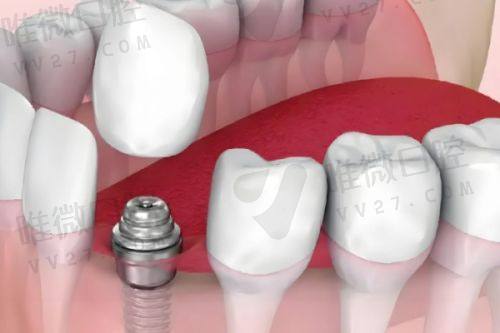

项目优势在于种植和正畸,医生技术稳定,而且价格合理:韩国登腾种植牙含冠仅从3680元起,相比市面动辄8000多的价格确实亲民不少。